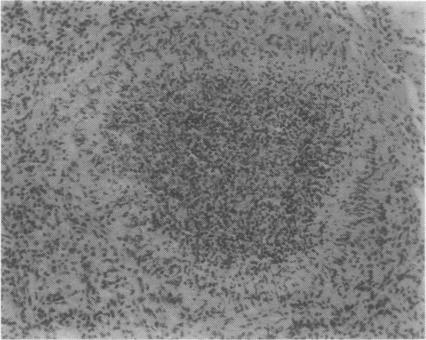

Among 173 consecutive open lung biopsies, nine gave a histopathological diagnosis of bronchiolitis. Seven of these patients had some connective tissue disorder (CTD), six of whom are presented in this report; two had classical and one possible rheumatoid arthritis (RA), one ankylosing spondylitis, one scleroderma, and one developed classical RA four years after biopsy. Four of the patients were smokers, most suffered from breathlessness and cough. In terms of lung function three patients had obstruction, one both restriction and obstruction and three a decreased diffusion capacity. For control purposes peripheral lung tissue was studied histologically from 24 consecutive smoking patients without CTD who underwent a lobectomy for cancer. Intraluminal plugs and mucosal lymphoplasmocytic infiltration of the bronchiolar walls were more prevalent and abundant in the CTD patients than in the controls (p less than 0.02 and p less than 0.001 respectively). Two CTD patients also showed some obliterative bronchiolitis. Corticosteroids were effective in one out of four patients treated. One patient improved and the others did not show any progression during the follow up. The results suggest that smoking alone does not explain the lesions of the small airways found in CTD patients, and that bronchiolitis may be specifically associated with the basic disorder in such cases.

在173例连续的开胸肺活检中,9例组织病理学诊断为细支气管炎。其中7例患者患有某种结缔组织病(CTD),本报告介绍了其中6例;2例患有典型类风湿关节炎(RA),1例可能患有RA,1例强直性脊柱炎,1例硬皮病,1例在活检后四年发展为典型RA。4例患者吸烟,多数有气促和咳嗽症状。肺功能方面,3例有阻塞性病变,1例有阻塞性和限制性病变,3例弥散功能降低。为作对照,对24例连续的因癌症接受肺叶切除术、无CTD的吸烟患者的外周肺组织进行了组织学研究。与对照组相比,CTD患者的细支气管腔内栓子和支气管壁黏膜淋巴细胞浸润更为普遍且更明显(分别为p<0.02和p<0.001)。2例CTD患者也显示有闭塞性细支气管炎。4例接受治疗的患者中1例对皮质类固醇有效。1例患者病情改善,其他患者在随访期间无病情进展。结果表明,单纯吸烟不能解释CTD患者中发现的小气道病变,在这些病例中细支气管炎可能与基础疾病有特定关联。